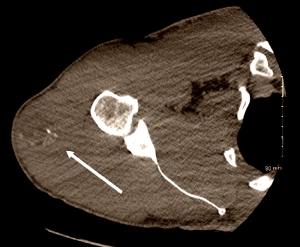

You can see the swelling in the scan below. Myositis ossificans was the diagnosis. The arrow points to an area of calcification.

Two weeks after the operation the bodybuilder announced that he had another lump in his left shoulder. Below you can see sagittal and coronal scans of that lump. It was identical to the lump that the doctors had removed from the bodybuilder's right shoulder and measured 16 x 11 x 3 centimetres.